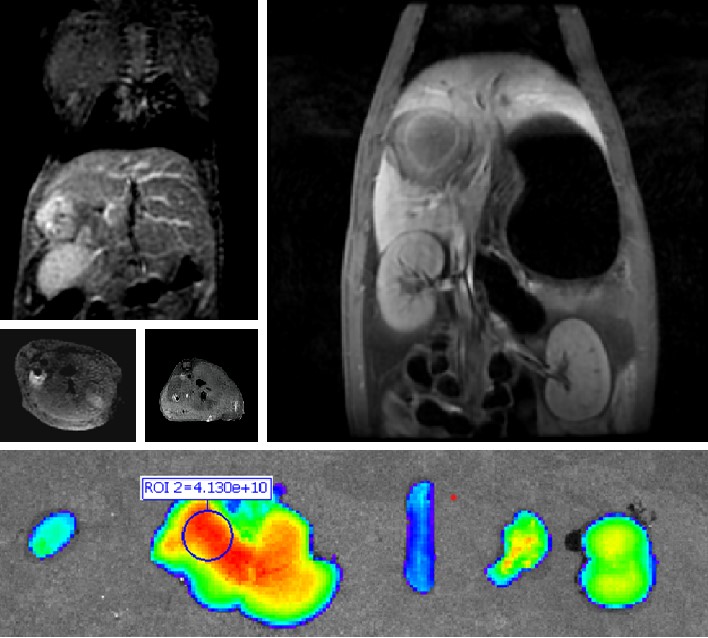

普利制药与浙江大学联合创制的胰腺癌纳米创新药PLAT001,首次构建了γ-谷氨酰转肽酶(GGT)介导的电荷反转聚合物,并将其应用于抗肿瘤药物的递送,突破纳米药物在实体瘤中的渗透性瓶颈。PLAT001目前已经获得中国和美国药物临床试验批件。

640 (8).jpg

普利制药自主研发双模态造影剂PL002,首次提出通过整合磁共振技术,弥补现有荧光染料假阳性率高、透射深度有限等的短板,进而提升手术的精确性,降低手术过程中的风险,是全球首个获批临床试验的荧光/磁共振双模态造影剂,目前也已经获得美国FDA临床试验批件

640 (9).jpg